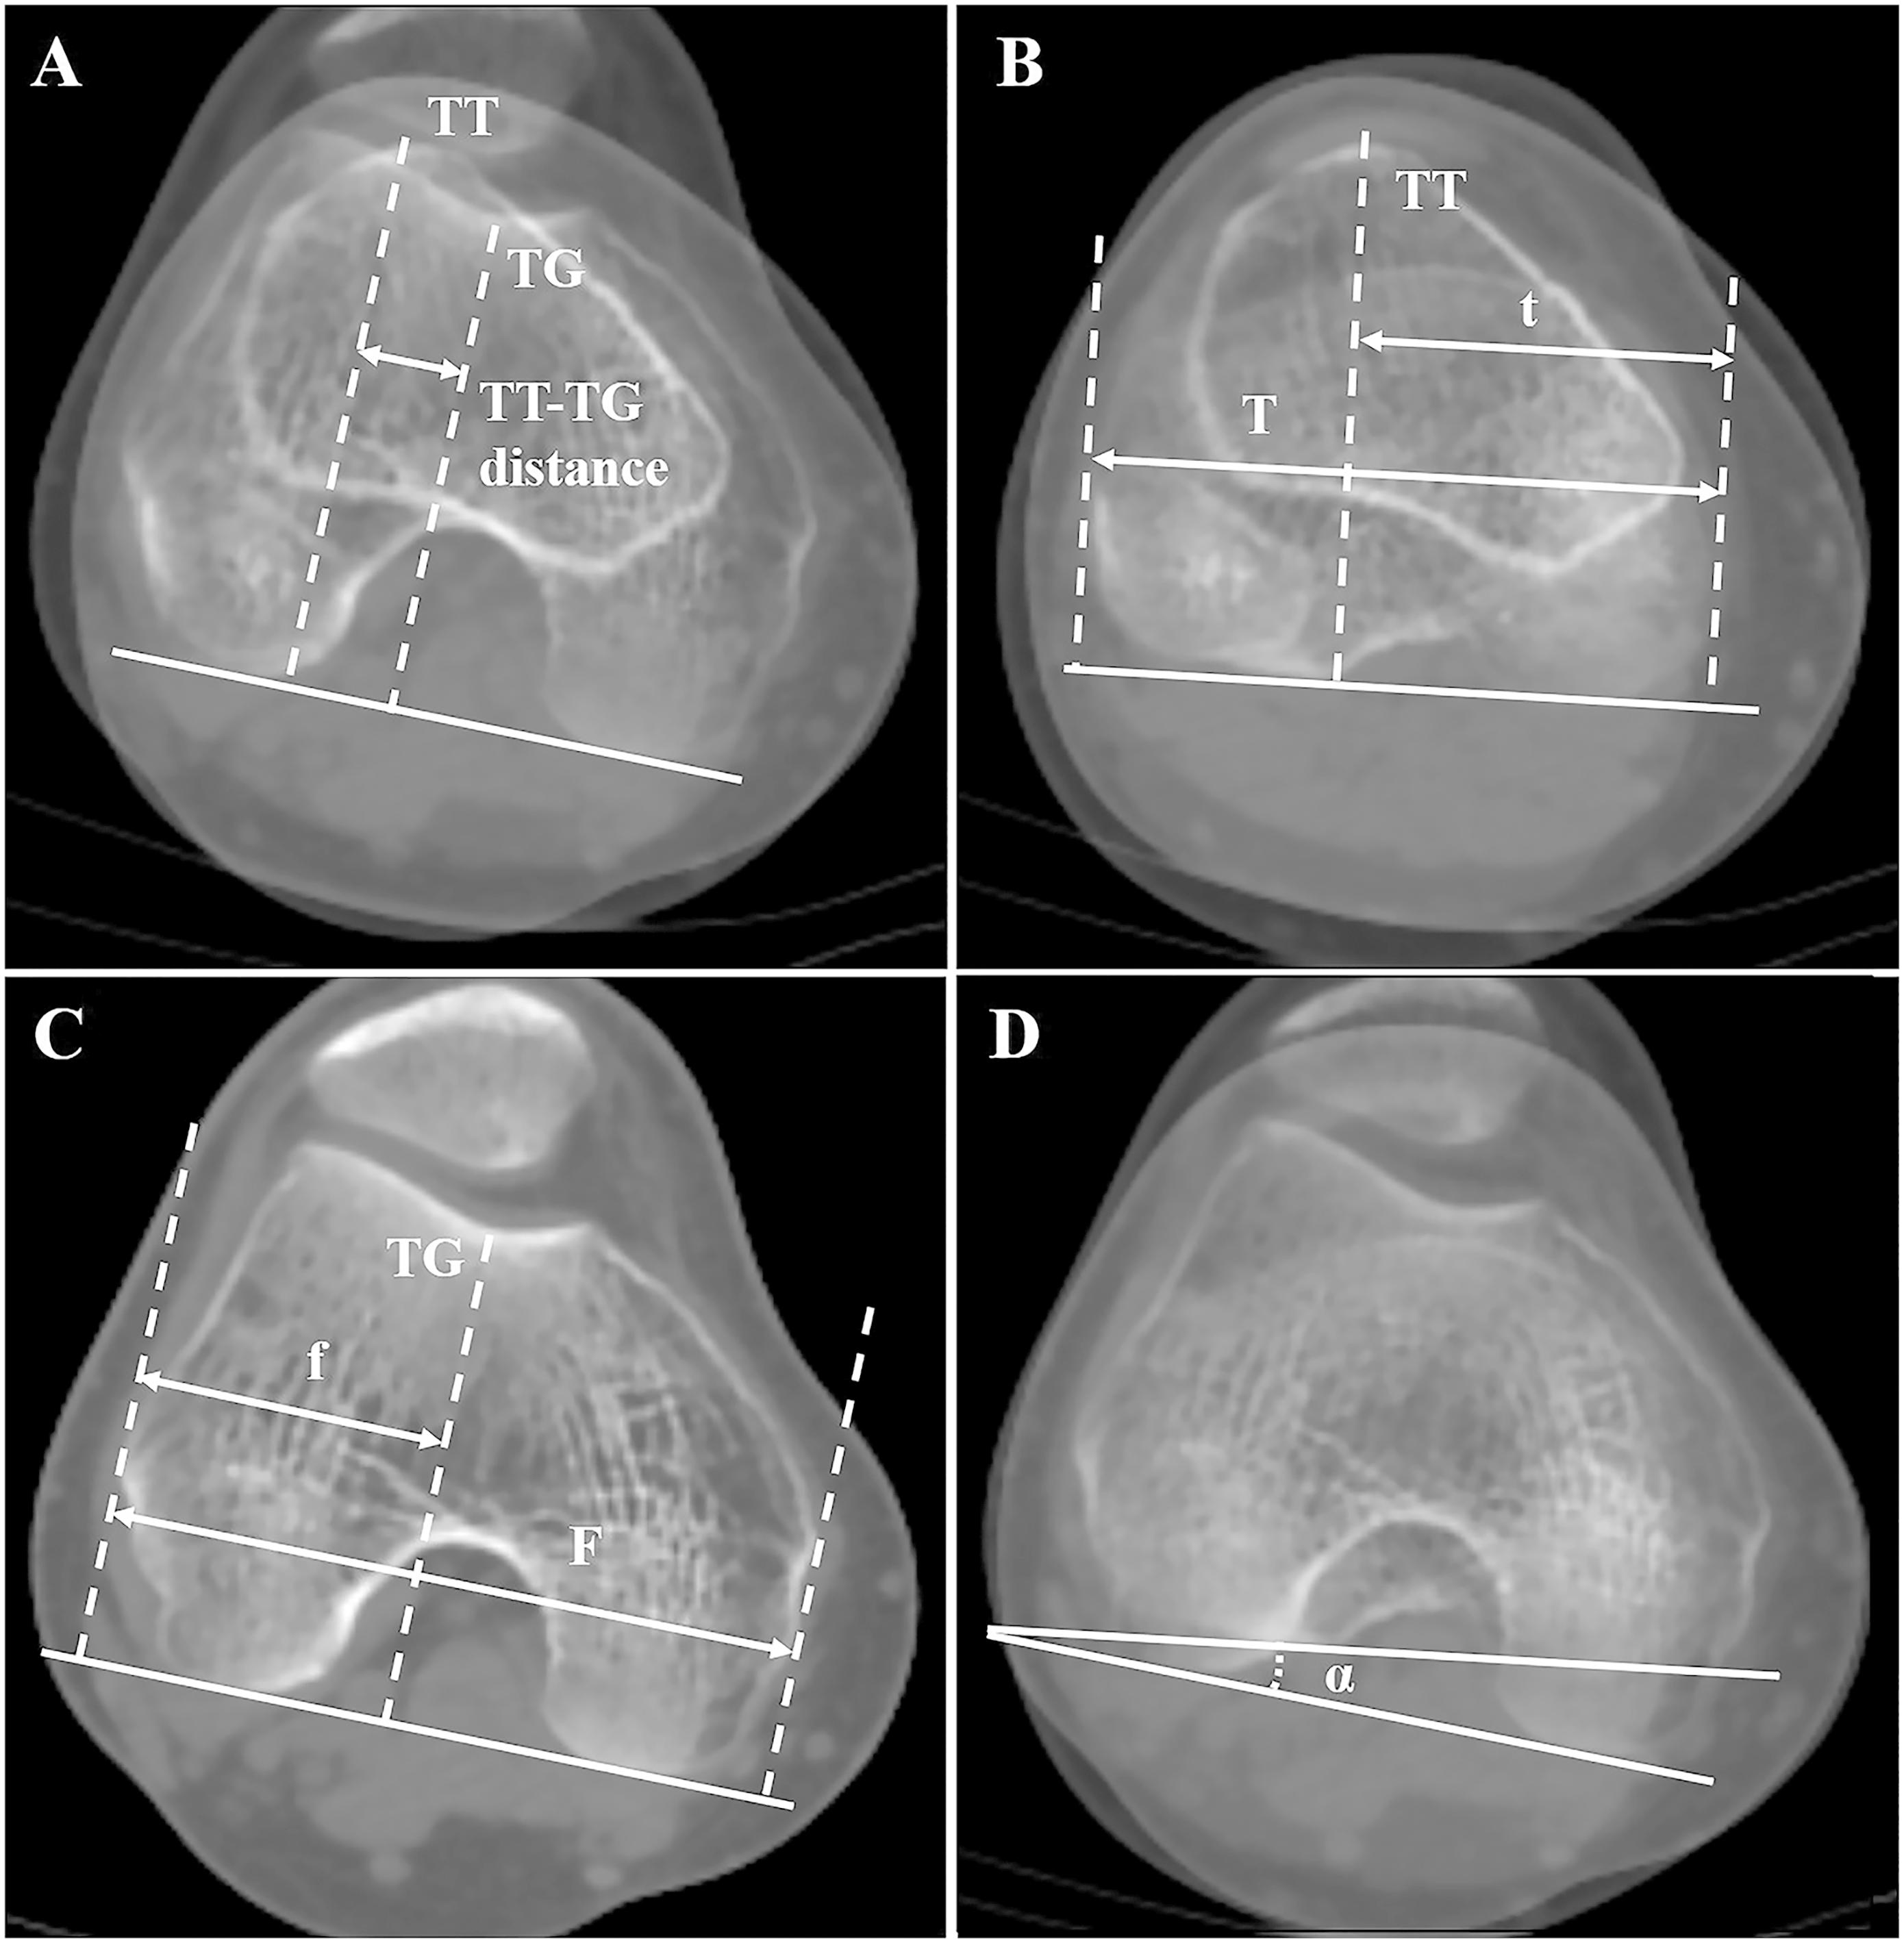

Tibial tuberositytrochlear groove distance measurement. Superimposed What Does Trochlear Groove Mean There is an invisible transition between what is normal and what is pathologic. An unstable kneecap can lead to a dislocated knee. When the kneecap slips out of the groove, recurrent instability (the kneecap dislocates often) and pain may result. Chondromalacia patella, more commonly referred to as runners knee, is a condition where the cartilage along the underside of the. What Does Trochlear Groove Mean.

Tibial tuberositytrochlear groove distance measurement the deepest What Does Trochlear Groove Mean When looking at the anatomy of the knee, the patella, or kneecap is designed to glide over a narrow groove on the top of the femur. Chondromalacia patella, more commonly referred to as runners knee, is a condition where the cartilage along the underside of the kneecap begins to soften and deteriorates over time. There is an invisible transition between. What Does Trochlear Groove Mean.

TIBIAL TUBEROSITY TROCHLEAR GROOVE DISTANCE What Does Trochlear Groove Mean When cartilage wears away, it becomes. This measurement between the tibial tubercle (place where the patellar tendon meets the bone) and the trochlear groove (the track in the femur for the patella) is a marker of how straight or. When looking at the anatomy of the knee, the patella, or kneecap is designed to glide over a narrow groove on. What Does Trochlear Groove Mean.

Variations in Tibial Tuberosity to Trochlear Groove and Posterior What Does Trochlear Groove Mean When the kneecap slips out of the groove, recurrent instability (the kneecap dislocates often) and pain may result. This measurement between the tibial tubercle (place where the patellar tendon meets the bone) and the trochlear groove (the track in the femur for the patella) is a marker of how straight or. Chondromalacia patella, more commonly referred to as runners knee,. What Does Trochlear Groove Mean.

The 3D measurement of tibial tuberositytrochlear groove distance What Does Trochlear Groove Mean An unstable kneecap can lead to a dislocated knee. The knees trochlear groove is the guide channel, into which the patella engages and glides. When looking at the anatomy of the knee, the patella, or kneecap is designed to glide over a narrow groove on the top of the femur. There is an invisible transition between what is normal and. What Does Trochlear Groove Mean.

Upper image shows the measurement of the tibial tubercletrochlear What Does Trochlear Groove Mean The kneecap connects the muscles in. When looking at the anatomy of the knee, the patella, or kneecap is designed to glide over a narrow groove on the top of the femur. When cartilage wears away, it becomes. Chondromalacia patella, more commonly referred to as runners knee, is a condition where the cartilage along the underside of the kneecap begins. What Does Trochlear Groove Mean.

CT scan to measure the tibia tuberositytrochlear groove distance What Does Trochlear Groove Mean The kneecap connects the muscles in. The knees trochlear groove is the guide channel, into which the patella engages and glides. Chondromalacia patella, more commonly referred to as runners knee, is a condition where the cartilage along the underside of the kneecap begins to soften and deteriorates over time. Page updated march 2024 by dr sheila strover (clinical editor) Trochlear. What Does Trochlear Groove Mean.